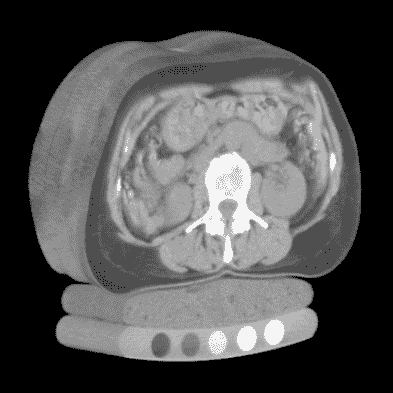

CT 扫描和 X 射线之间的主要区别在于,X 射线是将 3D 强度(在本例中为组织和骨密度)投影到 2D 平面上,而 CT 扫描保留了数据的第三维。这使我们能够以各种方式呈现数据:例如,作为一个灰度实体,我们可以在图 9.1 中看到。

图 9.1 人体躯干的 CT 扫描,从上到下依次显示皮肤、器官、脊柱和患者支撑床。来源:mng.bz/04r6; Mindways CT Software / CC BY-SA 3.0 (creativecommons.org/licenses/by-sa/3.0/deed.en)。